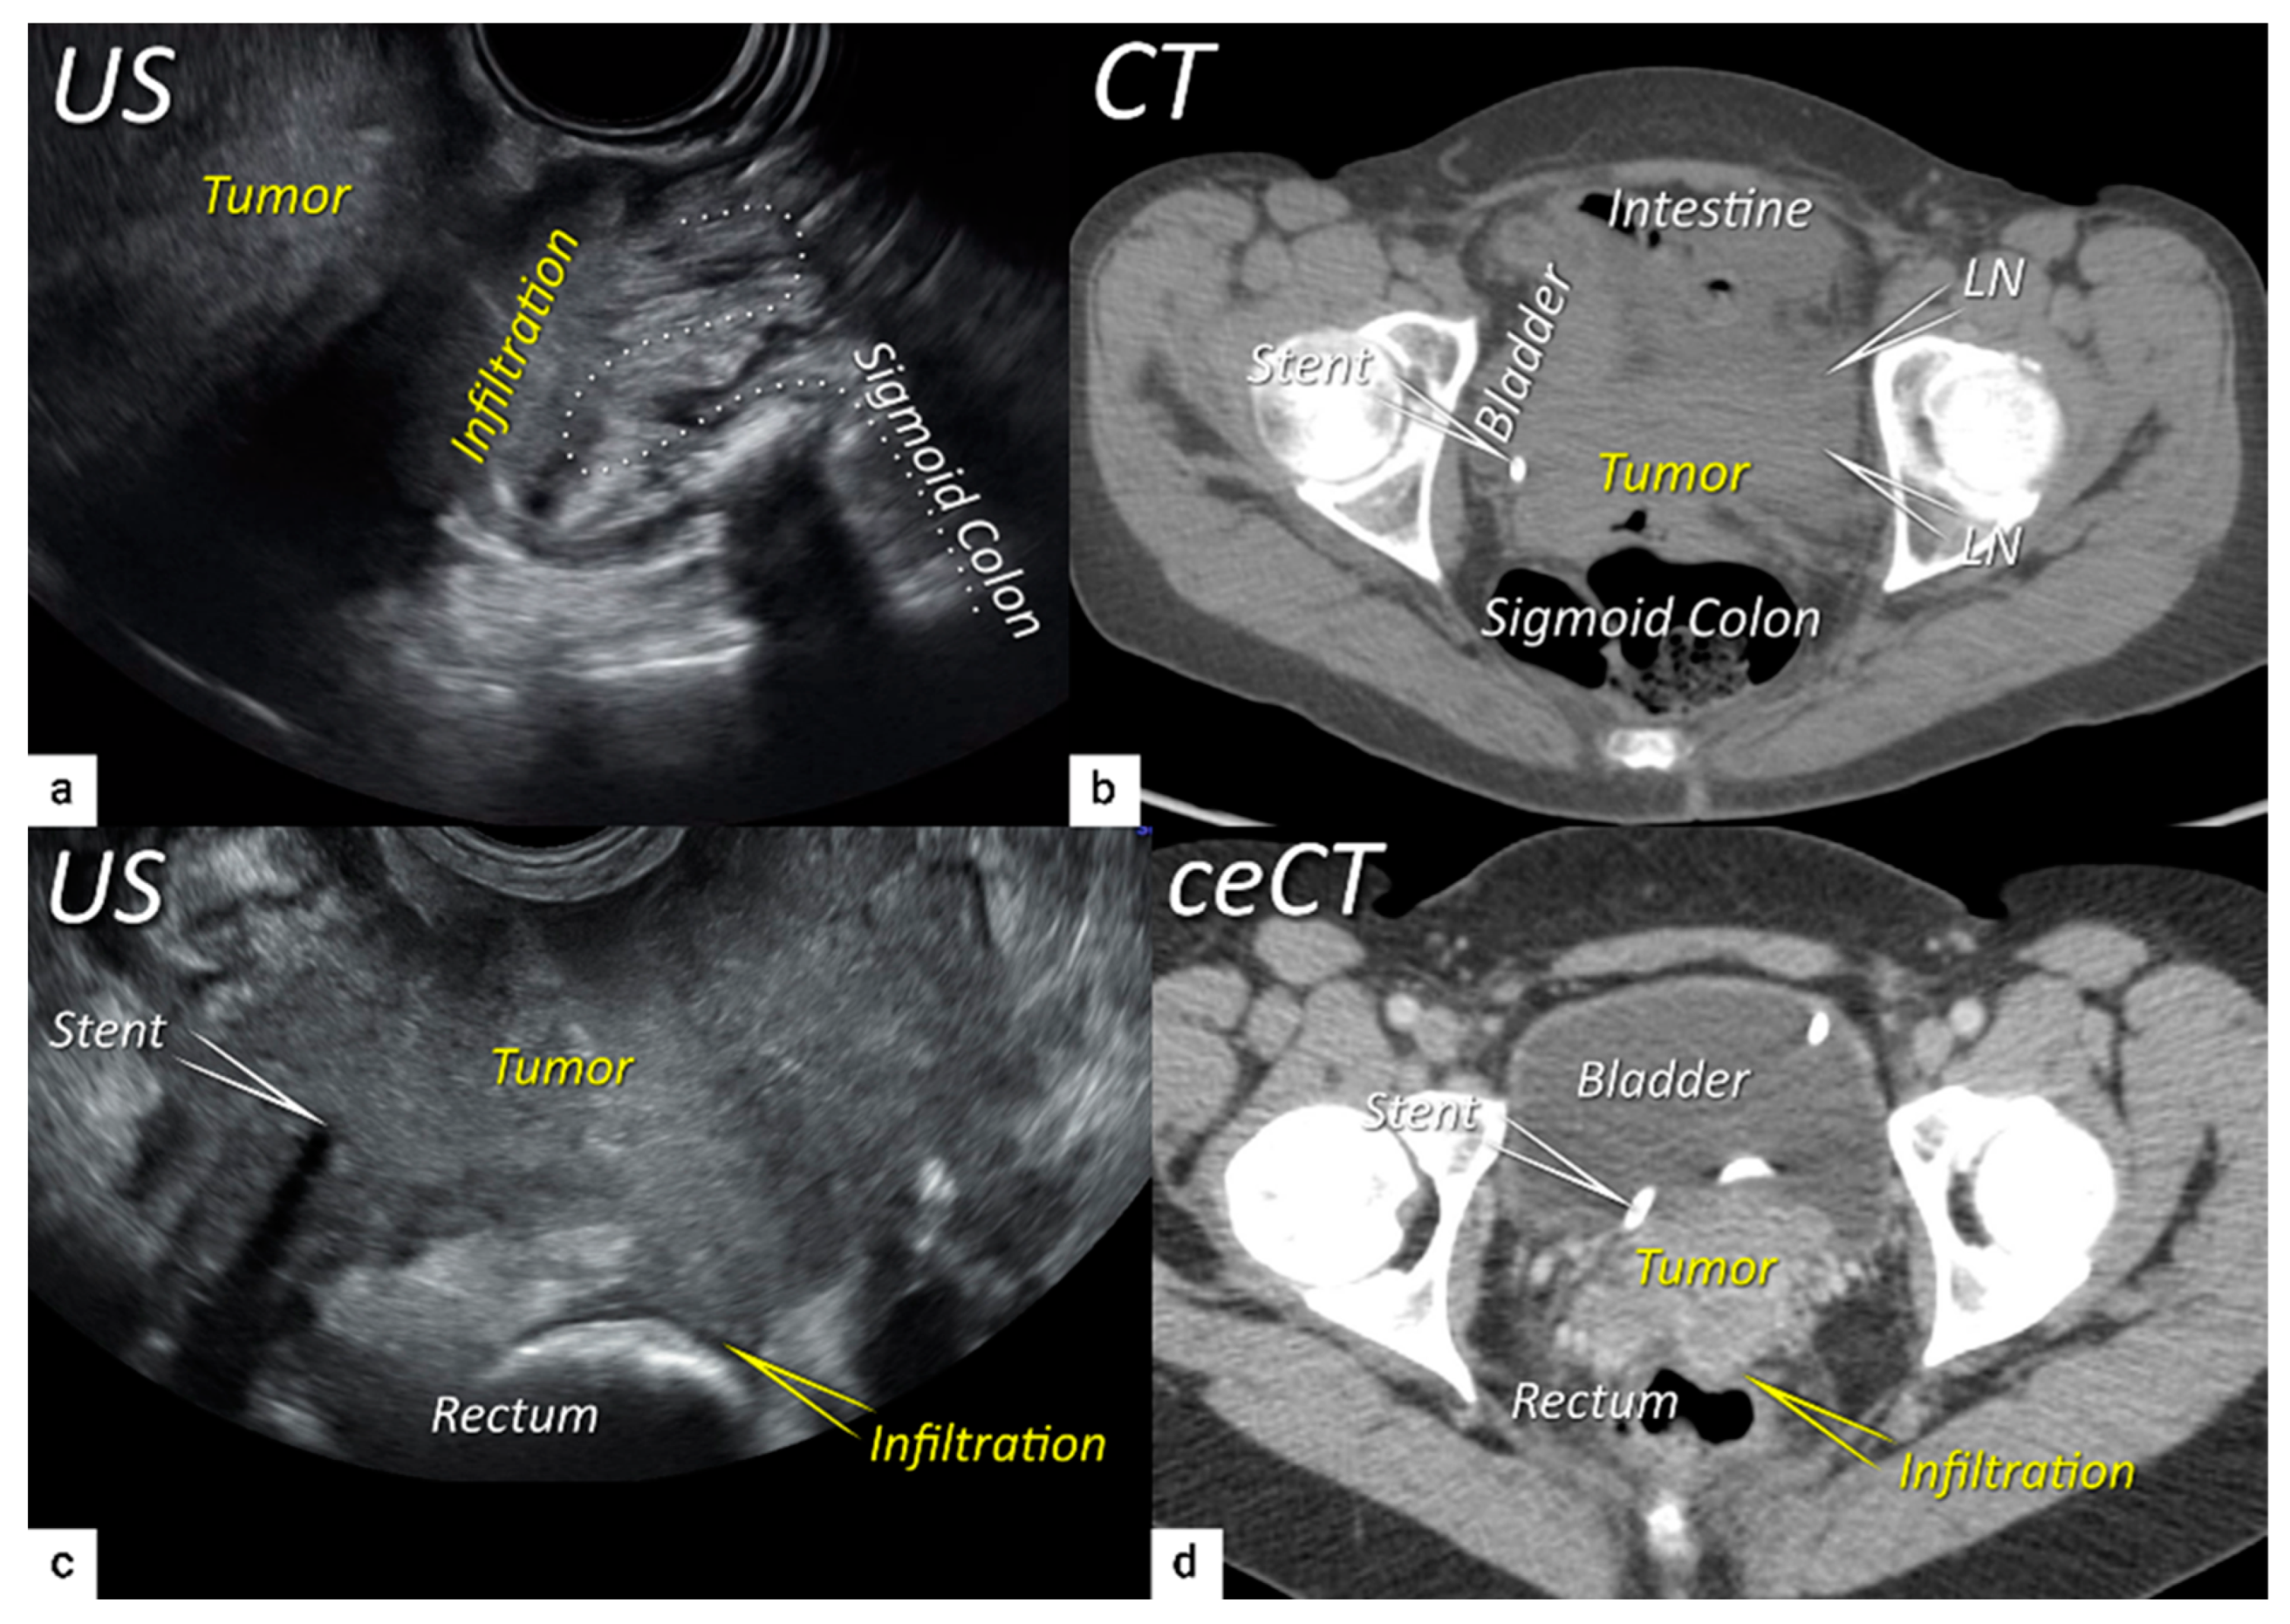

| T4 f | IVA f | Tumour invasion into the mucosa of the bladder or rectum (biopsy-proven) or into adjacent organs. | Tumour invasion into the mucosa of the bladder or rectum on imaging, confirmed by biopsy. US: Negative sliding sign, hypoechogenic tumour infiltration of bladder/rectal wall up to echogenic mucosa with polypoid tumour seen intraluminally. MRI: Focal or diffuse disruption of the normal T2-low signal intensity wall of the bladder/rectum, irregular or nodular wall, sometimes including an intraluminal tumour mass. Bulous edema sign, which is hyperintense thickening of the bladder mucosa on T2W images, is only an indirect sign of invasion and should not be regarded as T4 unless confirmed mucosal infiltration at cystoscopy. Infiltration of the posterior bladder wall without mucosal infiltration should not be regarded as T4a. |